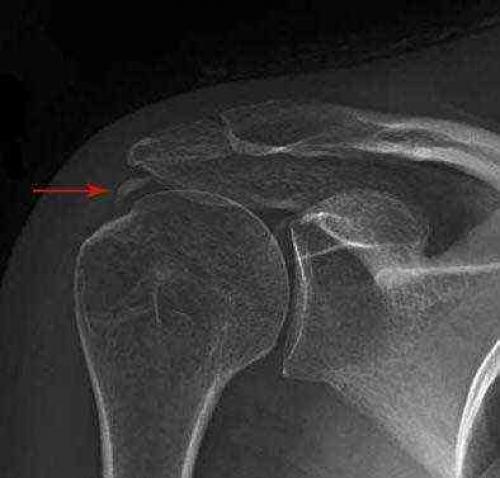

Самыми частыми причинами болей являются повреждения вращательной манжеты плеча – слоя сухожилий, окружающих плечевой сустав и отвечающих за сгибание, отведение и внутреннюю ротацию плеча.

Чаще повреждается сухожилие надостной мышцы, при падении на руку оно частично или полностью перерубается об акромиальный отросток лопатки, реже сухожилия подостной и подлопаточной мышц, перелом большого бугорка плеча, к которому прикрепляется сухожилие надостной мышцы, вызывает схожие симптомы. Эти повреждения сопровождаются болью в плечевом суставе и плече, ночными болями по типу зубной, встречались пациенты, которые могли спать только сидя, держа здоровой рукой больную. Также часто снижается объём движений в плече, человек не может поднять руку, причесаться, но, если сухожилие разорвано не полностью, движения в плече могут сохраняться в достаточном объёме.

Ещё к этому приводит повреждение связок и капсулы плечевого сустава (повреждение Банкарта, SLAP), в этом случае к боли и ограничению движений прибавляется чувство нестабильности в плечевом суставе, онемение в руке, нередки повторные вывихи плеча при обычных бытовых движениях.

Повреждение связок, фиксирующих ключицу к лопатке, так же сопровождается болью и нарушением функции.

Пациентам, имеющим подобные жалобы, необходимо обратиться за консультацией к ортопеду , который после подробной беседы и осмотра назначит необходимое обследование, чаще всего это рентгенография и ЯМРТ на аппарате мощностью не менее 1,5 Тесла, и порекомендует придти на повторный приём с результатами обследования.